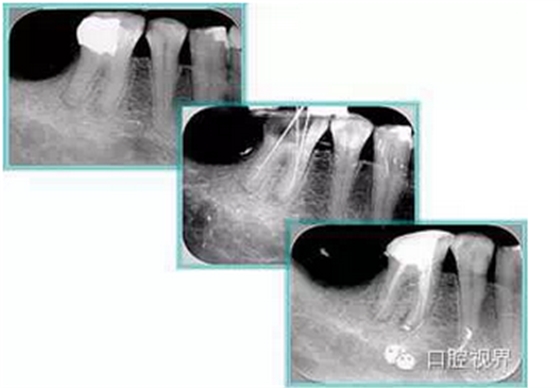

6. 術(shù)后 X 線片

術(shù)后 X 線片用來評定根管充填 長度、致密度(管壁清晰、側(cè)枝)等指標。

左圖為根管充填術(shù)后 X 線片。圖中可見,根管充填較好。右下圖有白色小點,為側(cè)方加壓導致糊劑擠出所致,表明根管充填比較致密。

致密、恰到好處的充填可去除干凈根管里感染灶,機體逐漸恢復。

多根牙時候需進行偏移投照,正位投照無法說明具體哪根牙根管充填效果。